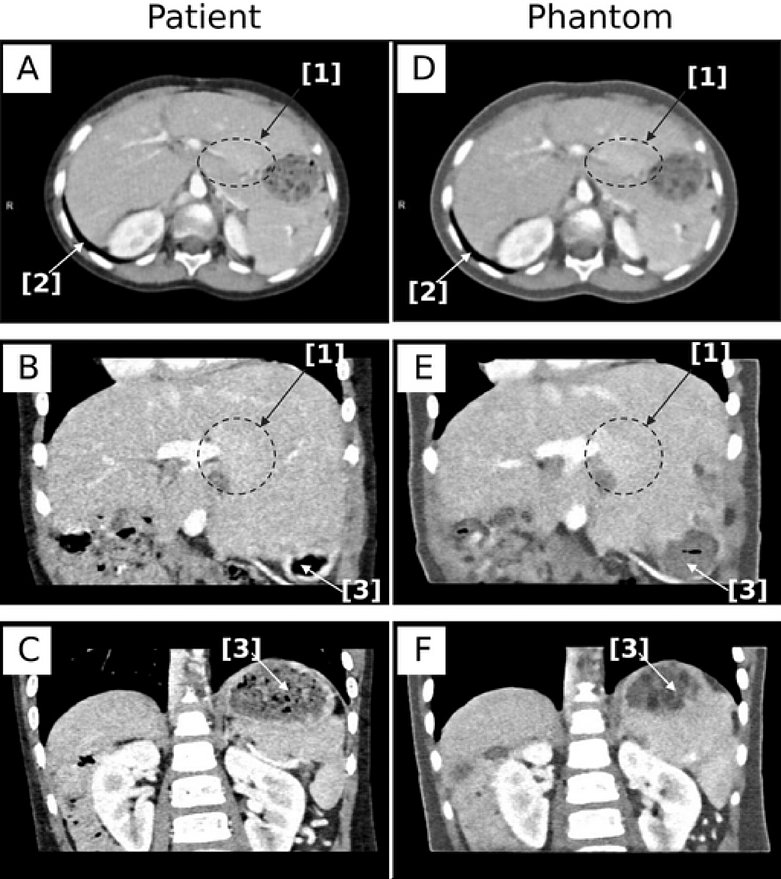

- 3D gedrucktes pädiatrisches Abdomen‑CT‑Phantom:

Basierend auf einem hochauflösenden PCCT-Scan eines realen Patienten konnte ein Modell des Bauchraumes 3D-gedruckt werden. Das Phantom ist eine detailgetreue Nachbildung des Bauchraums des Patienten und eröffnet neue Möglichkeiten: Beispielsweise kann man mithilfe des Phantoms Scan-Parameter optimieren. Das ist bisher nur mit Einschränkungen möglich.

- Schikorra T, et al. Validation of a novel 3D-printed anthropomorphic pediatric abdomen phantom using photon-counting CT. Sci Rep. 2025 Dec 12;15(1):43812. doi: 10.1038/s41598-025-32391-2